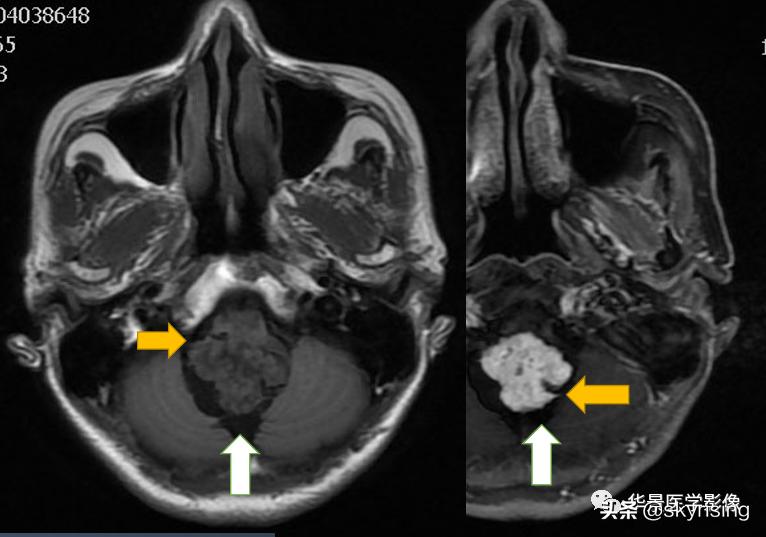

上图白色箭头:小脑延髓池内延髓背侧不规则形团块影,不均长T2信号,FLAIR条片样信号减低,提示水分子含量高。

黄色箭头:右侧细小流空血管信号;左侧较粗大贴边流空信号血管影。

上图白色箭头:小脑延髓池内延髓背侧不规则形团块影,延髓受压变形。

黄色箭头:走行与病灶边缘的流空信号血管影。